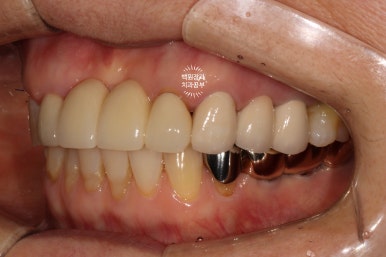

수술 전의 사진과 비교해서 생각보다 임플란트가 원래 자리와 비슷한 레벨에 위치해 있음을 확인할 수 있습니다.

정면에서 보았을 때는 잘 보이시지 않을 수 있으나,

측면에서 보았을 때, 처음에 저희 병원에 내원하셨을 때에 비해 많이 길어지지 않고 비슷한 길이의 크라운으로 제작된 것을 확인하실 수 있을겁니다.

수술 전에 비해 약 1-2mm 정도 임플란트 크라운이 길어진 느낌이네요.

체감이 잘 안되실 수 있으나... 치과의사들이 보면 나름 흥미로움을 느낄 수 있는 결과라고 할 수 있죠!

좌측은 깔끔하게 마무리된 지르코니아 브릿지를 보실 수 있네요 :)

씹는면에서 보면 그 깔끔함이 더 두드러집니다.